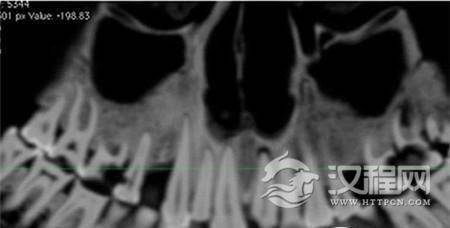

《古病理学国际期刊》的文章称,来自加拿大西安大略大学的安德鲁·韦德利用一种新型高分辨率CT仪扫描木乃伊的牙齿和身体,并且根据扫描片重建了3D图以进行更为细致的研究。从CT扫描片可以看到,木乃伊的一颗牙齿龋洞里塞着一块亚麻布团。这块亚麻布之前可能经过无花果汁液或雪松油等药物的浸泡,随后被塞入下颚第一、二颗臼齿中间,也就是最大、也是最疼的龋洞里。这么做既能起到抵挡食物残渣进入龋洞的屏障作用,又能利用亚麻布上的药物缓解疼痛。

早在20世纪90年代中期,就有研究人员发现了木乃伊口中的小麻布团,但当时的扫描技术太低以至于不能给出更全面的分析,而本次研究使用的高分辨率扫描仪的功能是之前扫描仪的6倍。